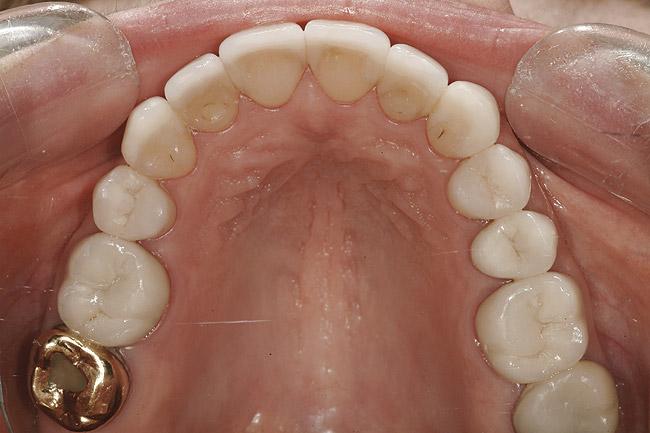

Pacienta a fost îndrumată pentru evaluarea ortodontică comprehensivă. Aşteptările tratamentului constau în nivelarea planului ocluzal maxilar, corectarea rotaţiilor şi a angrenajelor inverse şi alinierea dinţilor, cu îmbunătăţirea nivelurilor şi funcţiilor tisulare. Obiectivul primar al terapiei ortodontice era stabilirea poziţiei dentare ideale pentru tratamentul restaurator (fig. 10- 12).

Pentru această pacientă s-a recomandat ortodonţia cu scopul de a minimiza cantitatea de preparaţie dentară necesară în cazul în care dinţii rămâneau aliniaţi în malpoziţie. Dintr-o poziţie comprehensivă de planificare a tratamentului, reducerea masivă a structurii dentare slăbeşte dintele, amplificând astfel riscul biomecanic al pacientului, cu reducerea prognosticului pe termen lung5. Un rezultat estetic acceptabil este, de asemenea, mai puţin predictibil când se restaurează dinţi malpoziţionaţi.

Dinţii 1.6., 1.5., 1.3.-2.3. şi 2.6. au beneficiat de restaurarea bonturilor cu compozit. Dinţii 1.6., 2.5. şi 2.6. au fost preparaţi pentru coroane din zirconia stratificată, în timp ce 1.5.-2.4. au fost preparaţi pentru restaurări mai conservatoare din porţelan feldspatic. S-au realizat restaurări provizorii cu utilizarea unor chei polivinilice create pe baza wax-up-urilor diagnostice şi un material provizoriu bis-acrilic.